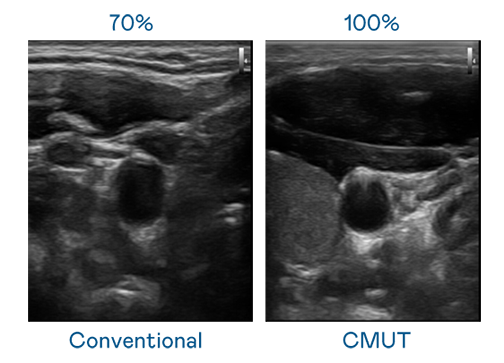

CMUT 技术是一种用电容式微机电元件来产生超音波讯号的技术。与传统 PZT 压电式技术相比,CMUT 频宽增加 30%,更宽频的超音波讯号让影像解析度大幅提升,是实现高影像品质医疗超音波扫描、促进精准医疗发展的关键技术。

大频宽带来超清晰影像

超音波影像的解析度高低,首先取决于探头能发出的讯号频宽。酷游官网 CMUT 可提供高清晰的超音波讯号,提供高频宽、高灵敏度、影像纹理细节更高的超音波影像,协助医护人员缩短影像判读时间及利用精准的医疗影像进行诊断。